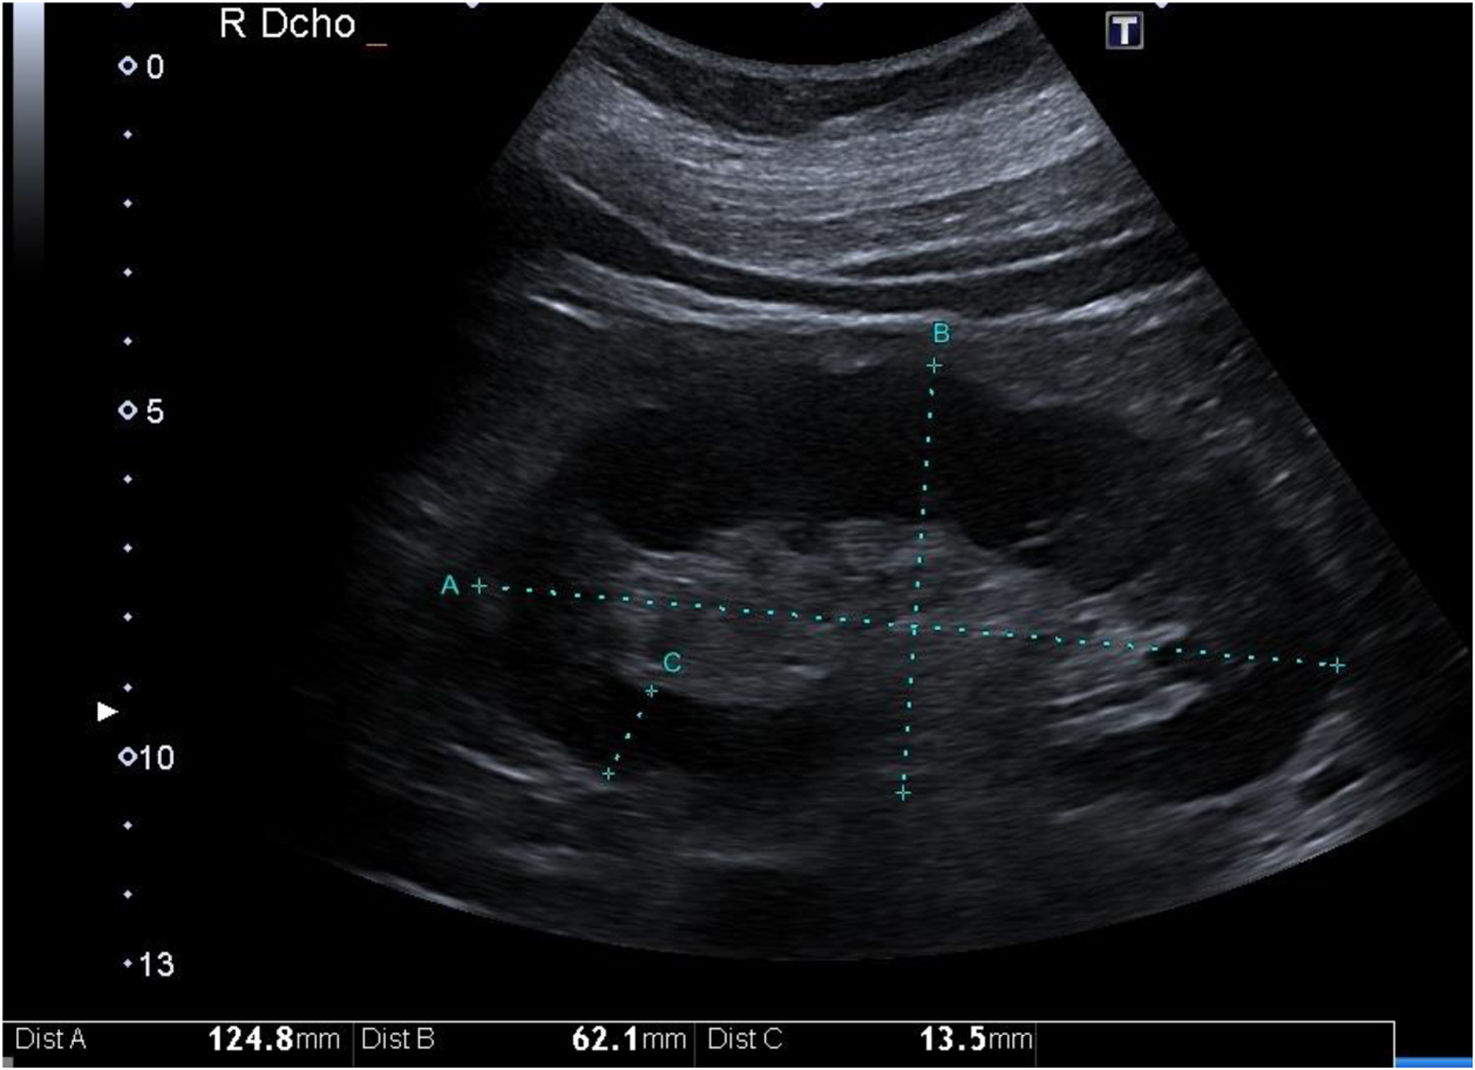

Parenchymal thickness, cortical thickness and kidney widthParenchymal thickness is correlated with the degree of CKD, and the strength of this correlation is significantly increased when the thickness is corrected for body height.1 It is also inversely associated with the degree of tubular atrophy. However, this is not the case for cortical thickness11 (Fig. 1).

The corrected parenchymal thickness is the only B-mode parameter (excluding parenchymal echogenicity) that decreases progressively as the eGFR increases. This parameter shows greater specificity according to receiver operating characteristic (ROC) curve analysis in distinguishing an eGFR lower than 60 mL/min than for distinguishing kidney length, cortical thickness, and kidney width. However, the corrected parenchymal thickness yielded a lower area under the curve (AUC) than did the echogenicity of the renal parenchyma.1,12